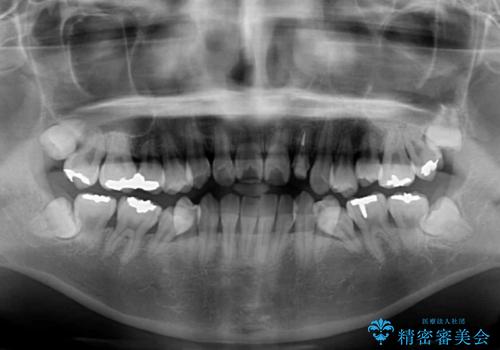

- 下顎の歯が舌側に倒れていることと、前歯の咬み合わせの不具合を気にして来院された患者様です。

受け口傾向の口元であるため、下顎左右小臼歯各1歯を抜歯して歯列を整えることとしました。

前歯には治療中の仮歯が装着されていたため、矯正治療後にオールセラミッククラウンにて補綴治療を行うこととしました。

抜歯矯正は2年から2年半程度の治療期間を要することが一般的ですが、僅か1年1ヶ月で終了しました。